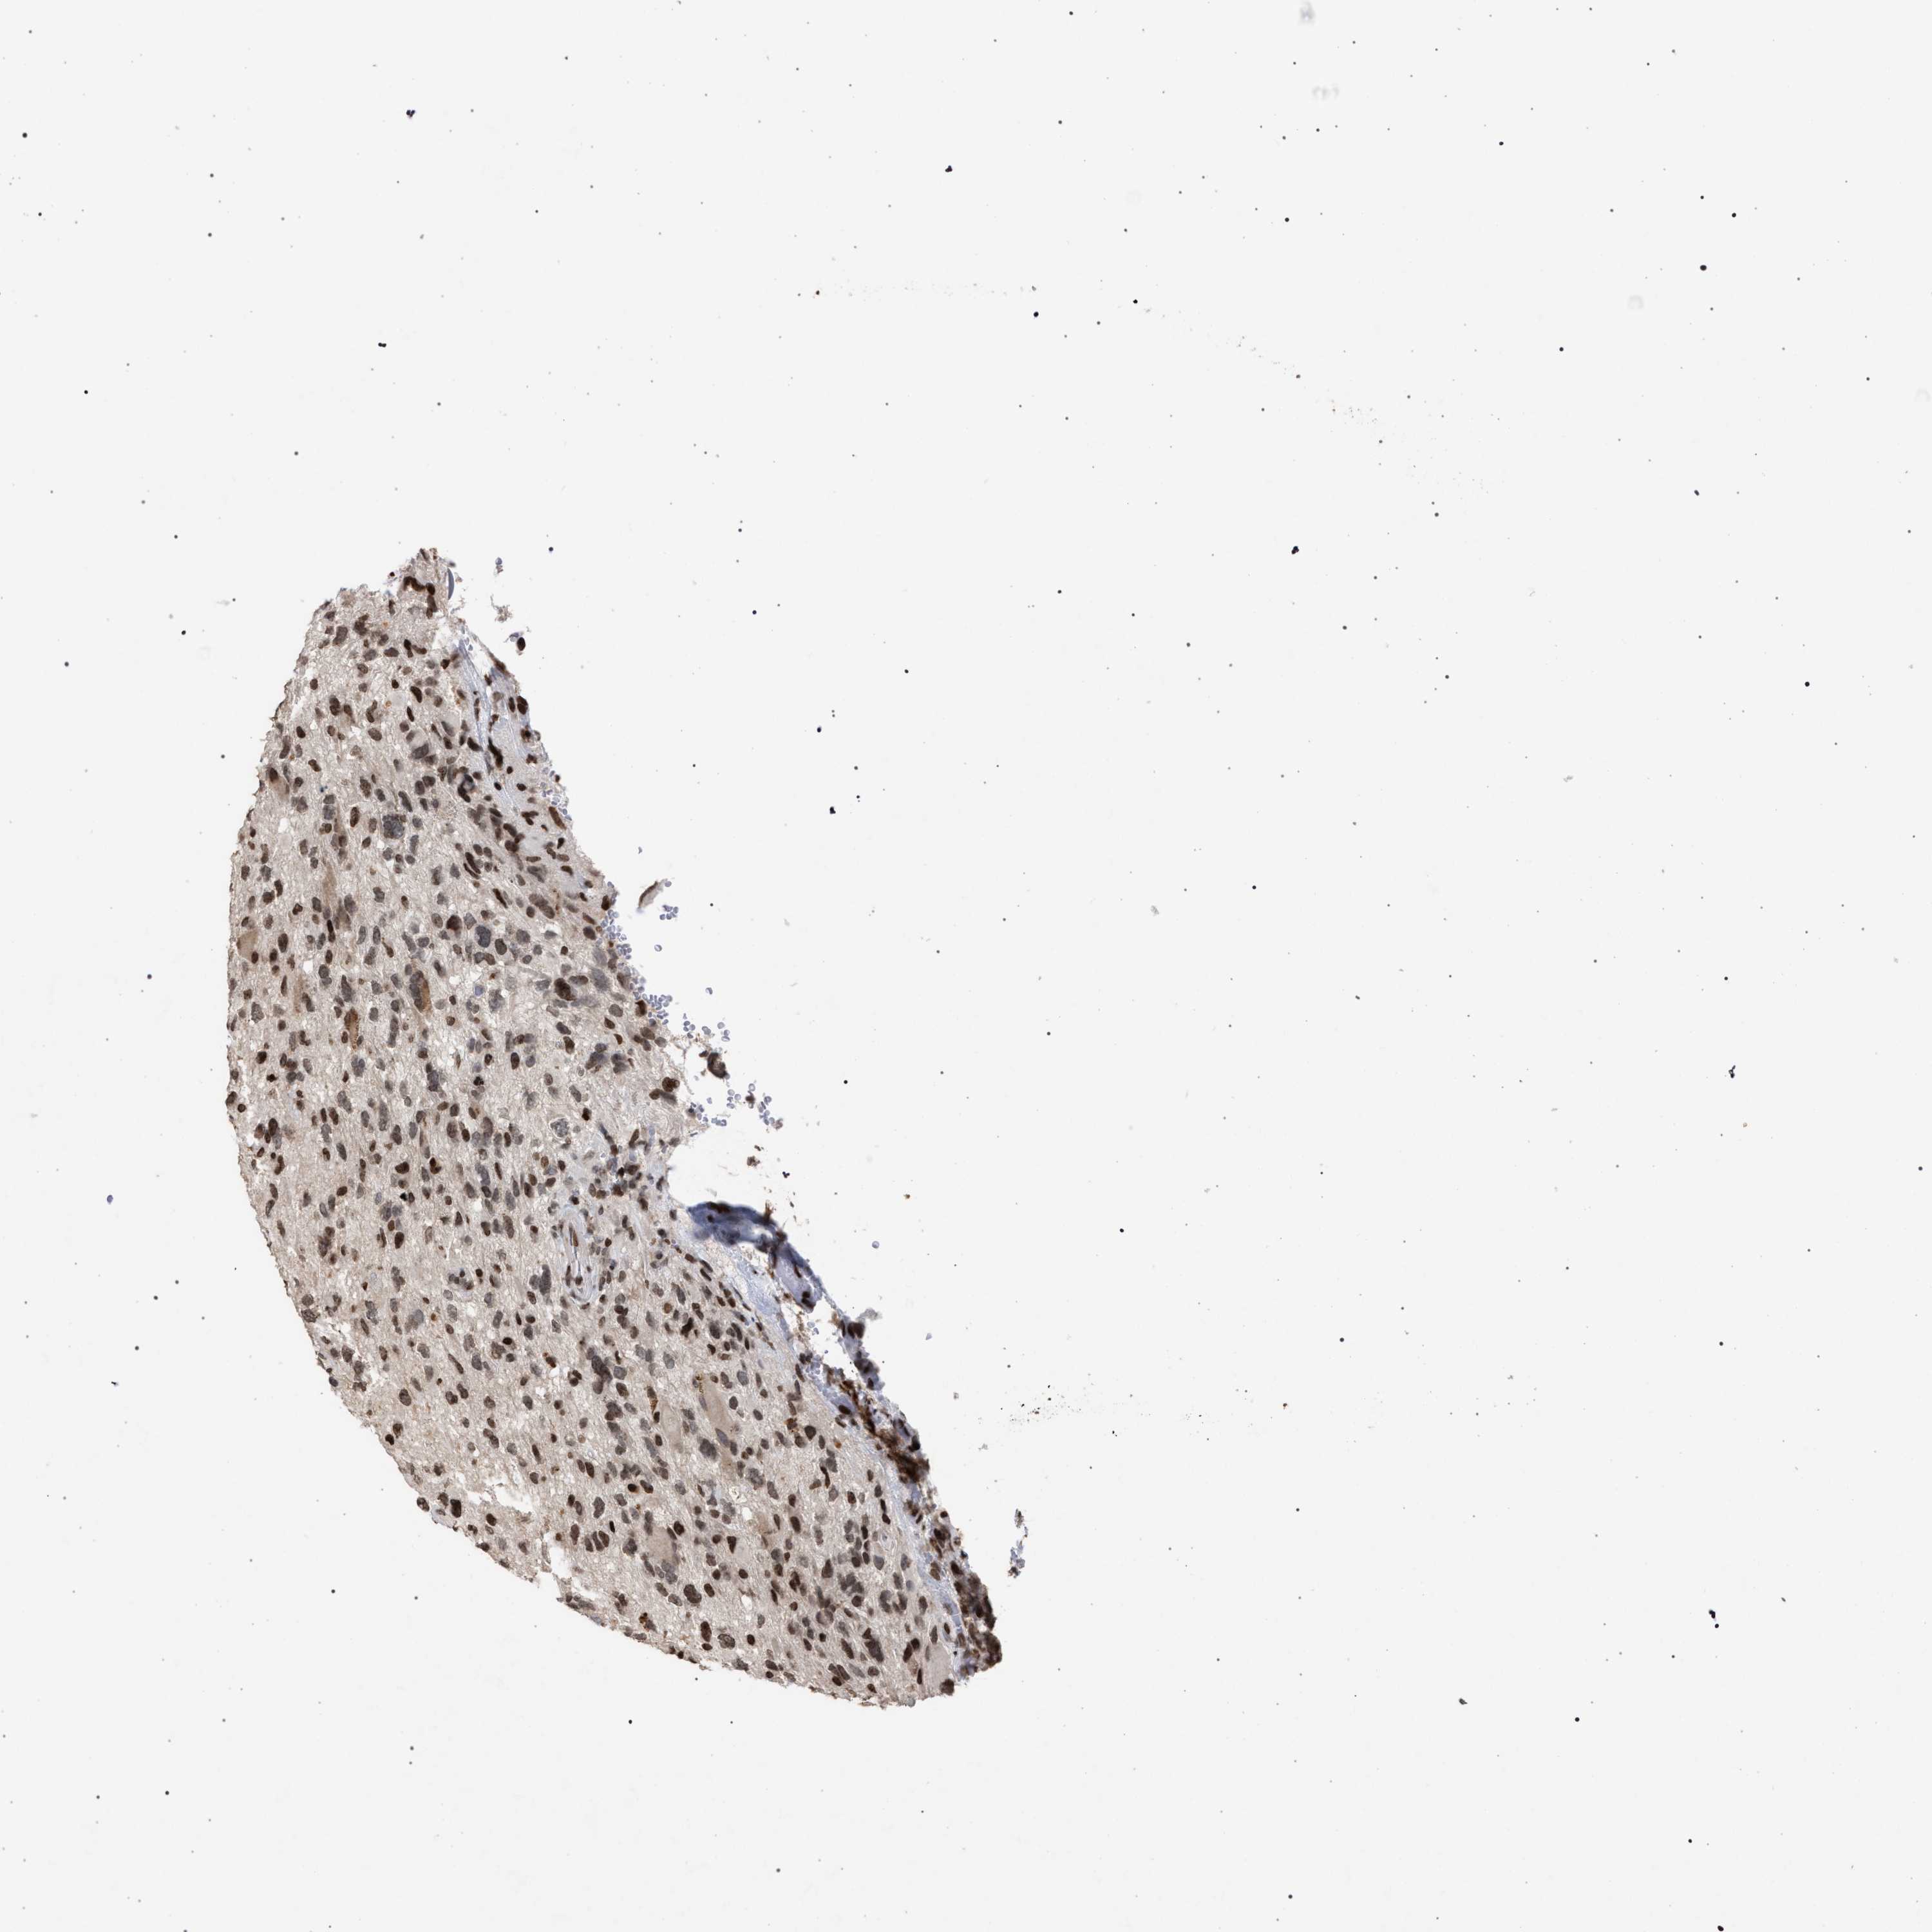

GLIOMA - Protein expressioni

A mouse-over function shows sample information and annotation data. Click on an image to view it in a full screen mode. Samples can be filtered based on level of antibody staining by selecting one or several of the following categories: high, medium, low and not detected. The assay and annotation is described here.

Note that samples used for immunohistochemistry by the Human Protein Atlas do not correspond to samples in the TCGA dataset.

Antibody stainingi

Antibody staining in the annotated cell types in the current human tissue is reported as not detected, low, medium, or high, based on conventional immunohistochemistry profiling in selected tissues. This score is based on the combination of the staining intensity and fraction of stained cells.

Each image is clickable and will lead to virtual microscopy that enables deeper exploration of all samples and also displays staining intensity scores, fraction scores and subcellular localization as well as patient and tissue information for each sample.

Antibody CAB022455

Staining

High

Medium

Low

Not detected

Intensity

Strong

Moderate

Weak

Negative

Quantity

>75%

75%-25%

<25%

None

Location

Nuclear

Cytoplasmic/membranous

Cytoplasmic/membranous,nuclear

Glioma, malignant, High grade

Glioma, malignant, Low grade